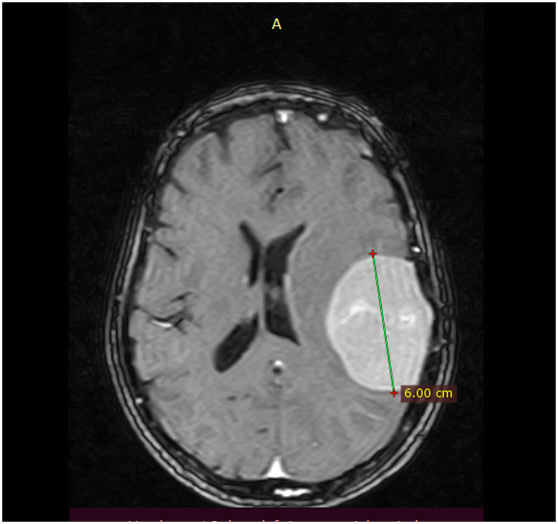

此前,该患者因长期头昏头痛到当地的普拉亚中心医院神经内科就诊,在完善了头颅CT和MRI检查后,医生判断其患脑膜瘤的可能性较大。

头颅MRI提示有脑膜瘤可能